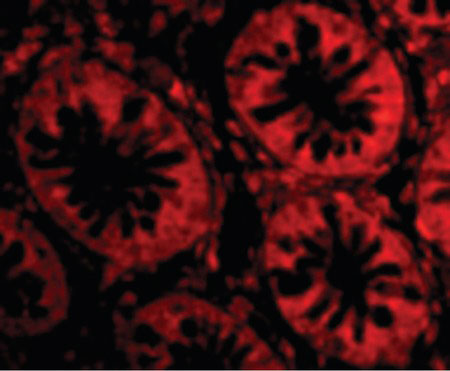

Images |

Immunofluorescence of TEM1 in Human Colon cells with TEM1 antibody at 20 ug/ml.

Anti-TEM1 antibody IHC of human pancreas. |